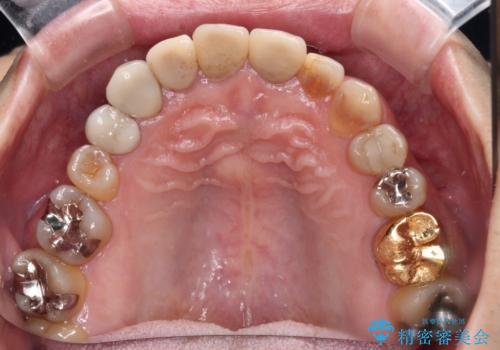

- 前歯のテトラサイクリンによる変色歯と、レジン充填の色の違いを気にして来院された患者様です。

患者様の希望により、前歯6歯をオールセラミッククラウンにて補綴することとしました。